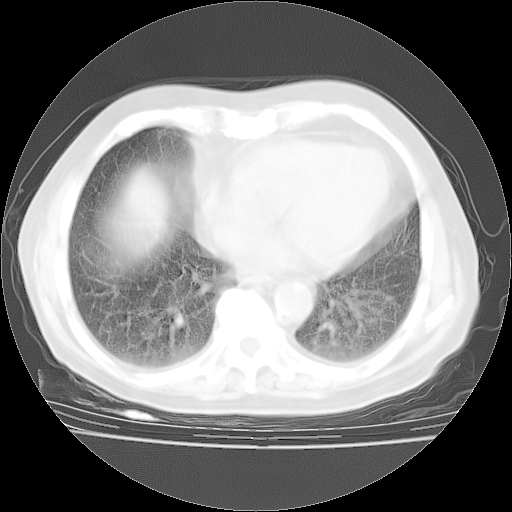

4月28日肺部CT——再次出现类似去年5月9日——透光度降低,“间质性”改变。

4月28日肺部CT——再次出现类似去年5月9日——磨玻璃样、间有“粟粒样”改变。

个人阅读4.14日肺部CT平扫:纵隔窗无异常,但肺窗示:双下肺内、后基底段有片絮状侵润影,部位以后基底段为著,以间质改变为主,呈急性肺泡炎征像,和首次住院影像学有相似之处。仅是个人读片,明日请相关专家再读片哈。其它建议同上。

1、108#的是4月14日的胸部CT(发此贴时还没看着28日的CT)。14日的胸部CT其实已经出现改变(如108#所述),个人认为28日的胸部CT除纵膈窗疑似有双侧胸膜增厚或少量胸积液(可行胸部B超明确)外,与4月14日对照病变有所加重;2、已经给予“异烟肼、利福平、乙胺丁醇”抗痨治疗?如果是,甲强龙80mg可缓慢减量;如果环磷酰胺已停用,暂不使用;3、中性粒细胞92%,明显升高,目前体温情况?注意合并细菌感染可能,使用左氧氟沙星情况下,是否联用B-内酰胺类抗菌药物?另外是查免疫全套非风湿全套。

今请临免主任会诊后认为:4月14日胸部CT已有双下肺间质性改变。患者病情复发多系激素减量过快不正规所致。目前甲强龙80mg/日,一周后酌情开始减量,不易过快。环磷酰胺若已停用,暂不使用。他同意目前抗菌药物使用,但应考虑是否加用B-内酰胺类抗菌药物(中性细胞明显增高);2、结核复发目前依据不足;3、若免疫全套各项指标正常,考虑多系特发性肺间质炎可能大。4、加强支持,并注意保护胃黏膜。